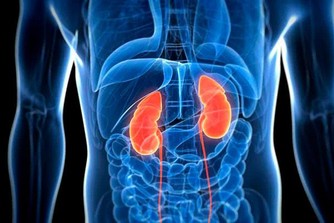

不少人喜歡在辦公桌上放一些像布洛芬或萘普生這樣的止痛藥。確實,當頭痛、背痛或腰痛時,這些非甾體類抗炎藥物可以讓你舒服一些。但長期服用高劑量止痛藥,不僅會出現胃腸道問題(噁心、便秘),還可能有更嚴重的並發症,如潰瘍甚至腎衰竭。當然,疼痛的時候你也沒必要硬扛著,只要嚴格按標籤服用即可。然而,如果服用超過10天,最好看醫生。